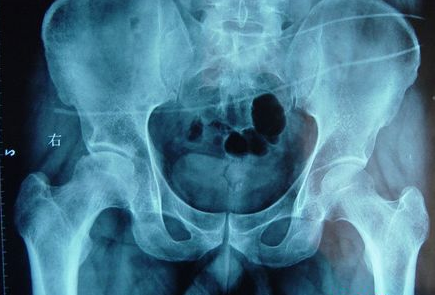

股骨头坏死的症状有哪些?河南股骨头坏死专科医院哪

河南股骨头坏死专科医院介绍股骨头坏死是较为常见的骨科疾病,多数患者有长期酗酒史、激素…[详情]

股骨头坏死怎么治疗?郑州痛风风湿病骨科医院

郑州痛风风湿病骨科医院介绍首先对股骨头坏死的病因做一个具体阐述。股骨头坏死最常见的是…[详情]